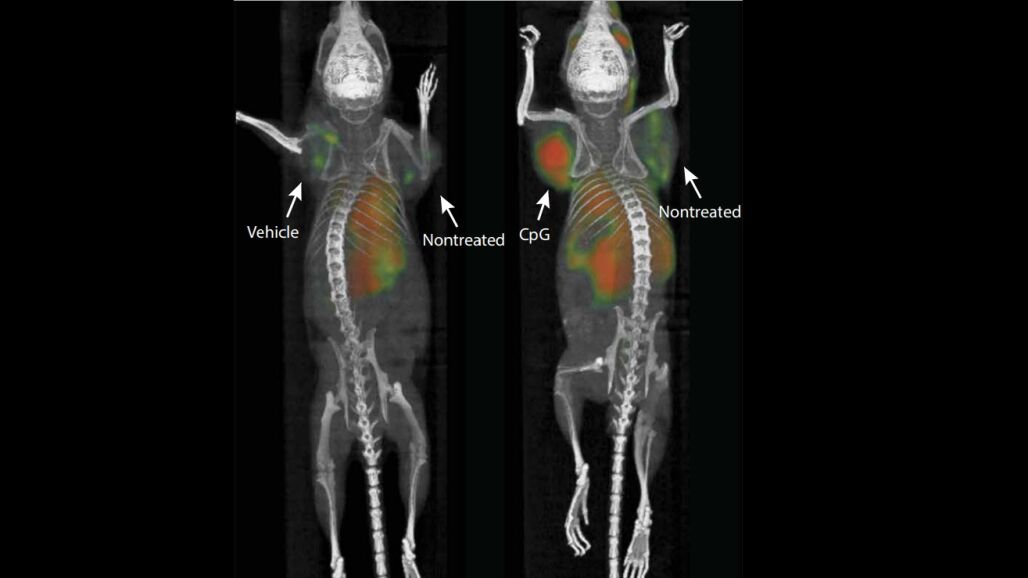

Después de inyectar una combinación de dos refuerzos inmunes directamente en tumores sólidos de ratón, el equipo de investigación ha asegurado que la vacuna ha conseguido eliminar todos los rastros del cáncer específico del cuerpo del animal, incluidas las metástasis que no se habían tratado previamente.

Cuando un sistema inmune detecta células cancerosas en el cuerpo, sus células T atacan el tumor, pero, con el tiempo, el tumor diseña formas de dominar las células inmunes y continúa creciendo. En este experimento, las células T que combaten el cáncer del sistema inmune se rejuvenecieron cuando se inyectó una cantidad de microgramos (una millonésima parte de un gramo) de los dos refuerzos inmunes en un tumor de linfoma de ratón. Esas mismas células luego se movieron desde el tumor que destruyó para encontrar cualquier otro tipo de cáncer idéntico en el cuerpo. Aunque la inyección fue exitosa en la eliminación de los tumores presentes en el ratón, las células T no pasaron a un tumor de cáncer de colon también encontrado en el animal.

El experimento se replicó en otros 90 ratones y logró erradicar los tumores en 87 de ellos, lo que permitió a los investigadores declararlos libres de cáncer. El cáncer recurrió en tres de los animales, pero los tumores retrocedieron luego de otra ronda de tratamiento inmunológico. El estudio también fue exitoso en ratones que tenían tumores de mama, colon y melanoma.